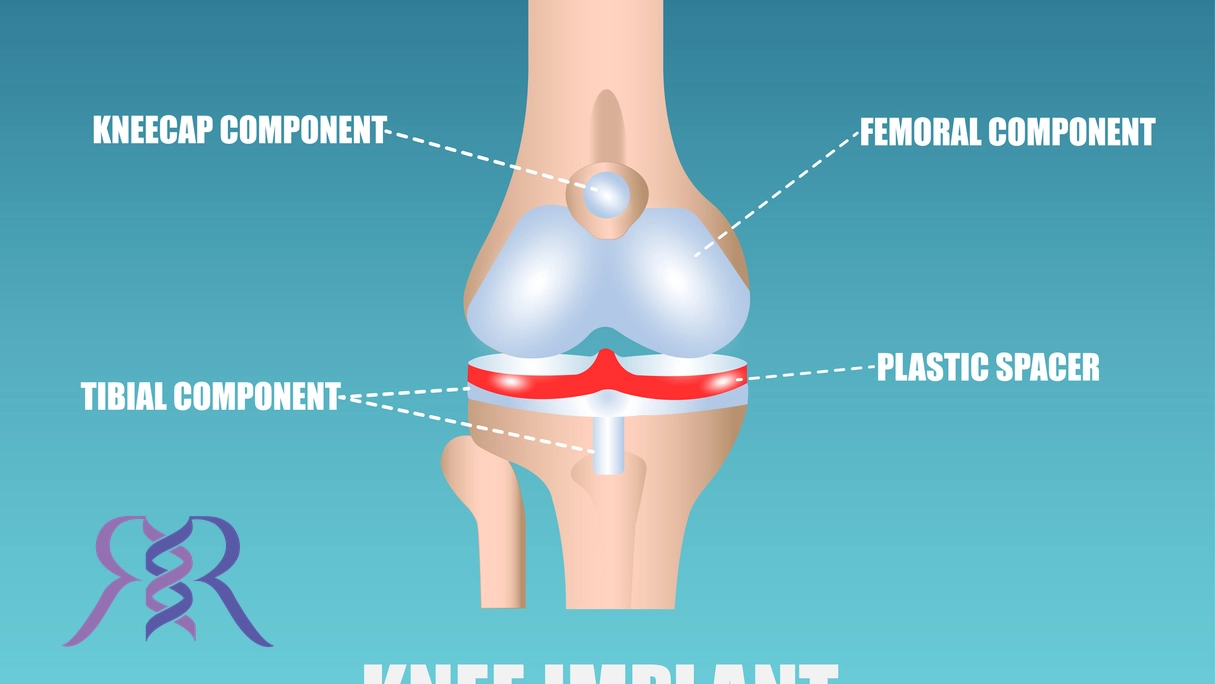

پروتز زانو دستگاه مصنوعی است که برای جایگزینی مفصل زانو در بیماران مبتلا به آرتروز یا آسیبهای جدی به کار میرود. این پروتز از قطعات فلزی، پلاستیکی و سرامیکی ساخته شده که عملکرد مشابه مفصل طبیعی زانو را تقلید میکند. پروتز زانو به گونهای طراحی شده است که به کاهش درد، افزایش حرکت و بازگرداندن عملکرد طبیعی زانو کمک کند. این درمان عمدتاً برای افرادی که به دلیل بیماریهای مختلف مانند آرتروز یا آسیبهای شدید مفصل زانو نمیتوانند به راحتی راه بروند، انتخاب میشود. در نتیجه، پروتز زانو یکی از مهمترین و پیشرفتهترین گزینههای درمانی برای مشکلات زانو به شمار میرود.

پروتز کامل زانو به طور کامل مفصل زانو را جایگزین میکند. این نوع پروتز برای بیمارانی که تمام قسمتهای مفصل زانو دچار آسیب یا بیماریهای شدید مانند آرتروز پیشرفته شدهاند، مناسب است. در این نوع پروتز، سطوح مفصلی که شامل استخوانهای ران، ساق پا و کشکک زانو هستند، با مواد مصنوعی از جمله فلزات، پلاستیکهای مخصوص و سرامیکهای مقاوم جایگزین میشوند. این پروتز برای بیماران مسنتر یا افرادی که مشکل شدید در عملکرد زانو دارند، انتخاب میشود.

این نوع پروتز به دلیل طراحی خود، عملکرد طبیعی و راحتی بیشتری را برای بیمار فراهم میکند و میتواند به بهبود تحرک و کاهش درد کمک کند. در این پروتز، سطوح مفصل زانو به گونهای طراحی میشود که هم از نظر عملکردی و هم از نظر ساختاری مشابه مفصل طبیعی باشد.